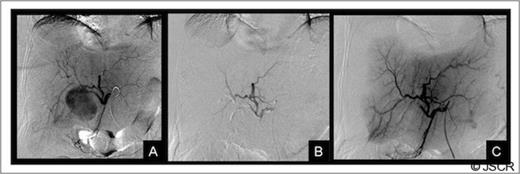

Given these findings an arteriography was performed confirming pseudoaneurysm of the right anterior hepatic artery. The patient then underwent embolization and occlusion of the RHA with coils and an Amplatzer Vascular Plug (AGA Medical, Golden Valley, MN) (Figure 3).

Liver arteriography: A) Selective arteriography of the common hepatic artery showing a pseudoaneurysm of the right anterior hepatic artery, B and C) Result after embolization with coils and an Amplatzer vascular plug. The figure shows a complete occlusion of the pseudoaneurysm and the right anterior hepatic artery.